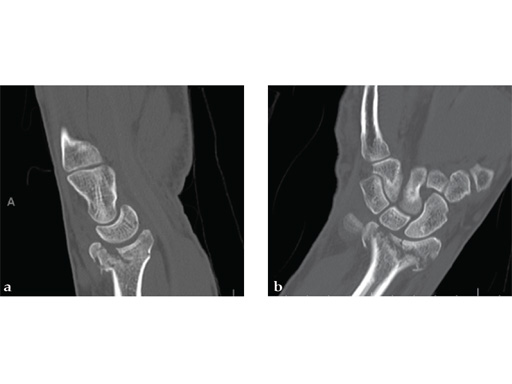

Case 2: A 44-year-old man sustained polytrauma following a car accident. Among his injuries was a distal radial fracture, Mller AO Classification 23-C1.

Case provided by Vitezslav Ruber, Brno, Czech Republic